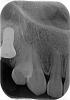

Nafania Опубликовано 18 мая, 2011 Автор Поделиться Опубликовано 18 мая, 2011 Сегодня сняли коронку, опять качали головами, что коронка хорошая, головные боли не от нее и зубы подвинутся не могли. Субъективно сразу стало лучше. Меня очень беспокоят трещины на зубах (сильно заметны при ярком солнце, снять фото пока не удалось). Сделали снимки передних верхних зубов - сказали все нормально , но меня беспокоит один зуб. Уважаемые врачи, прокомментируйте, пожалуйста, есть ли повод для беспокойства Здесь снимок трещин (правда не все видны, их гораздо больше ) и коронки - на месте "5". Ссылка на комментарий

Nafania Опубликовано 19 мая, 2011 Автор Поделиться Опубликовано 19 мая, 2011 (изменено) От трещин в эмали мне порекомендовали использовать мусс GC и сказали, что трещины есть у всех. А вопрос количества - дело субъективное. Хотя я и остаюсь при своем мнении, что коронка "добавила" это количество . Подскажите, пожалуйста, есть ли повод к беспокойству за передние зубы на основании рентгеновских снимков? Мне сказали, что все нормально (разговор велся по-английски - и здесь все всегда - нормально). Но при проверке (не уверена как называется точно - когда в чем-то смоченный кусочек марли прикладывают к зубам) один зуб реагировал не сразу, как остальные, а с примерно 4-секундной задержкой. (Справедливости ради надо сказать, что этот зуб некоторое время назад стал темнее, чем другие) Внизу снимок импланта и "3" до установки коронки. В верхнем сообщении - снимки после установки.И еще вопрос (прошу прощения, если уже задавался раньше, но весь форум я прочитать пока не успела). КАК пациенту определить что коронка "правильная"? В моем случае, как определить "правильность" контакта с соседними зубами? У меня это первый опыт, мне сказали, что несколько дней может идти привыкание - и я честно ждала А внешне - все выглядело почти прекрасно...Теперь жалею... Надо было на следующий же день снимать...Сейчас стоит "healing" абатмент, и зубы явно "подвинулись" назад, головные боли прошли! Честно сказать, боюсь опять ставить коронкуИзвините, очень много написала. Спасибо, что дочитали. Изменено 19 мая, 2011 пользователем Nafania Ссылка на комментарий